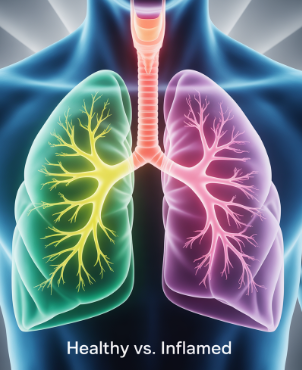

폐렴은 폐에 세균, 바이러스, 곰팡이 같은 병원체가 침투해 염증이 생기는 질환이에요. 특히 면역력이 떨어졌을 때 쉽게 걸리며, 노인, 어린이, 만성질환자에게 위험합니다. 감기나 독감이 오래가면서 폐렴으로 악화되는 경우가 많고, 요즘은 코로나 이후에 폐렴으로 이어지는 사례도 종종 보고되고 있어요.

폐렴은 감기와 달리 증상이 더 길고 심합니다. 감기는 보통 5~7일 내 호전되지만, 폐렴은 시간이 갈수록 증상이 심해지고 열도 쉽게 떨어지지 않습니다. 또, 호흡할 때 숨이 차거나 가슴 통증이 있는 경우는 감기보다는 폐렴일 가능성이 높습니다. 특히 노인 분들은 열이 뚜렷하지 않고 기력 저하만 나타날 수도 있어 더 주의가 필요합니다.